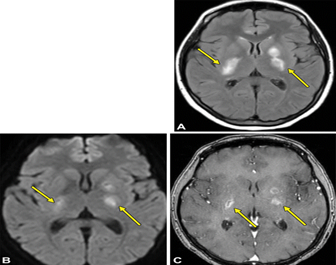

Bệnh nhân nữ 39 tuổi bị lupus ban đỏ hệ thống, có biểu hiện đau đầu, chóng mặt, hoa mắt, không yếu liệt, không sốt. Được chụp phim MRI sọ não có tiêm thuốc đối quang. Hình ảnh tổn thương chất trắng dưới vỏ thùy thái dương, chẩm, đỉnh trái, tăng tín hiệu trên xung T2W, FLAIR, giảm trên xung T1W, không hạn chế khuếch tán trên xung Diffusion, không ngấm thuốc đối quang từ sau tiêm. Bệnh nhân được chẩn đoán viêm não hủy myelin chất trắng/SLE, được điều trị bằng corticoid, các triệu chứng lâm sàng giảm.

Hình số 1, 2: chuỗi xung FLAIR đám tổn thương chất trắng ở thùy thái dương, chẩm đỉnh bên trái, tăng tín hiệu

Hình số 3: DWI không hạn chế khuếch tán

Hình số 4: chuỗi xung T1W sau tiêm thuốc đối quang từ tổn thương không ngấm thuốc